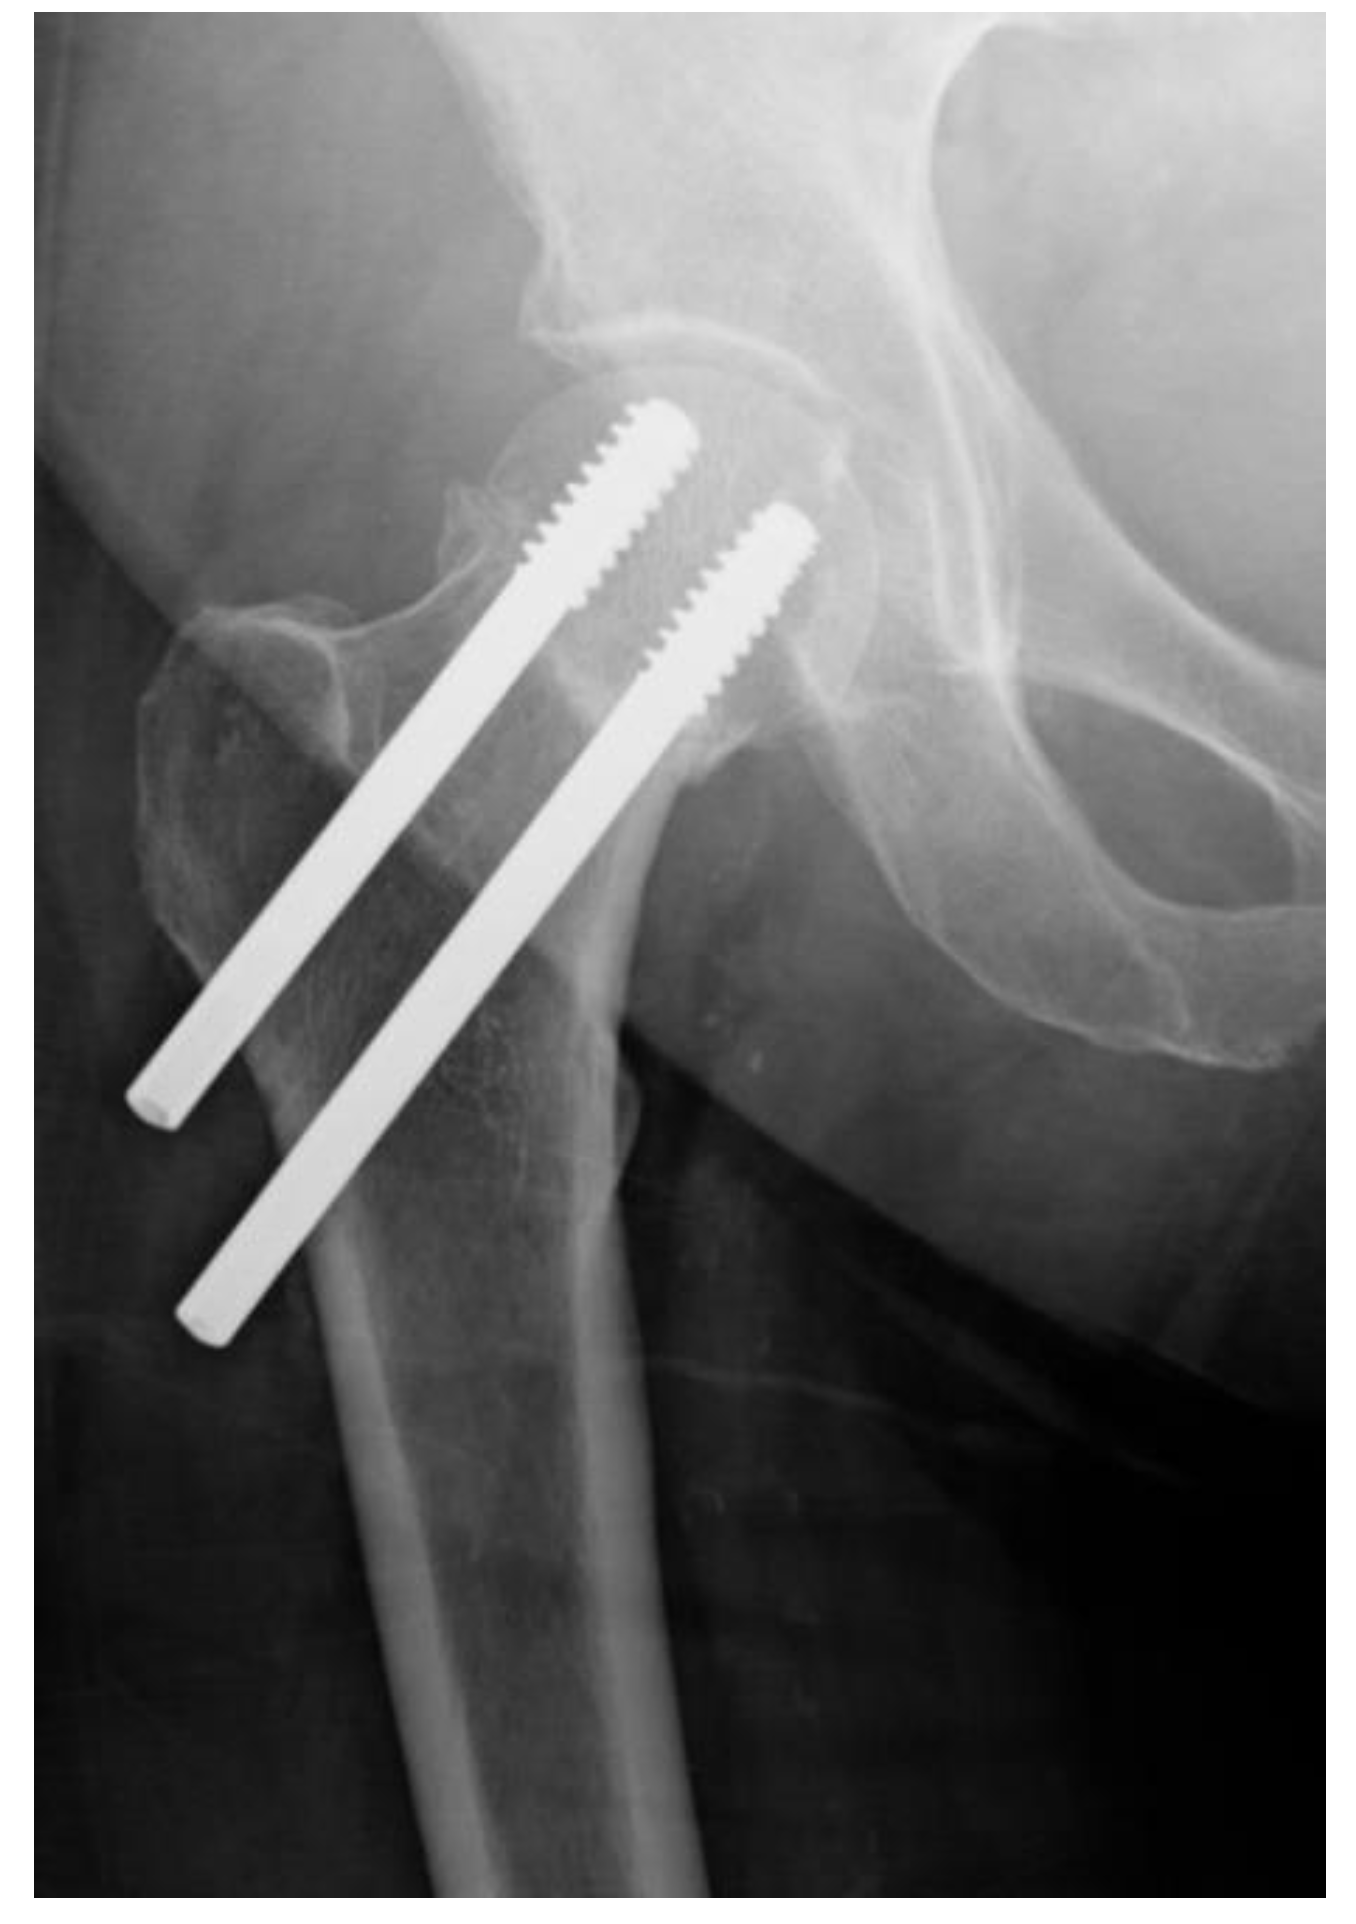

Usually it is implanted after closed reduction on a fracture table under image intensification. The dynamic hip screw (DHS), a femoral head-sparing orthopaedic device, is used to treat femoral neck fractures

Synthes Dynamic Hip Screw. Dynamic Sliding Hip Screw Device Explained Clearly w/ Dr. Sanders Note: Keep continuous forward pressure on the DHS / DCS wrench while advancing the lag screw The Dynamic Hip Screw from Depuy Synthes is intended for the fixation of proximal femoral fractures